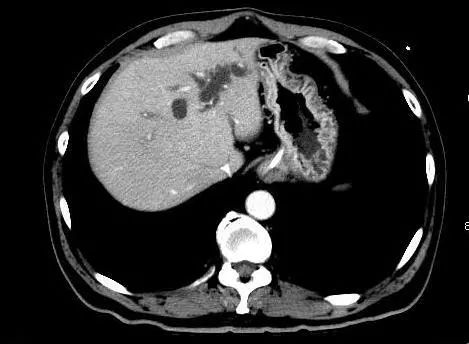

全腹部增强CT提示:肝门汇管区肝总管及胆总管上段管壁增厚伴强化,左半肝管扩张。

上腹部MRI增强提示:肝门汇管区肝总管管壁增厚伴狭窄,左半肝管扩张伴胆管炎。住院过程中查抗HEV-IgM、IgG双阳性,诊断急性戊肝。

图1 患者影像学检测结果

但该患者明显的左肝内胆管的扩张并不能以此诊断解释。反复多次的影像学检查,ERCP并未发现梗阻性病灶。而患者目前的肝功能已接近正常,尤其是ALP已在正常范围内,TBIL、GGT接近正常,似乎也不支持肿瘤性病变诊断。可扩张的左肝内胆管也难以用肝内胆汁淤积来解释,在此留下了疑问。